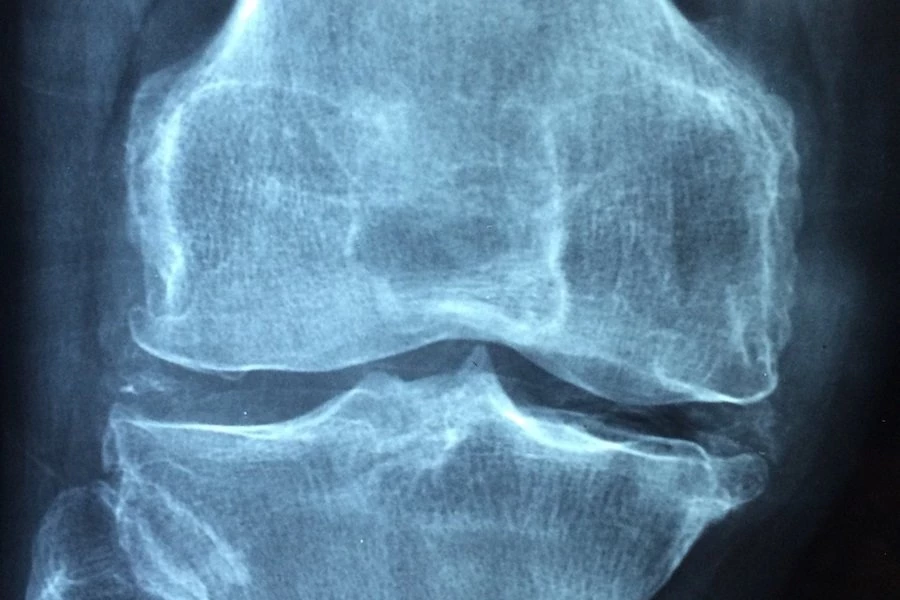

Учёные США нашли бактерии, атакующие хрящевую ткань при ревматоидном артрите

Ученые заметили, что у пациентов с серьезными формами ревматоидного артрита в их кишечнике обнаруживается большое количество бактерий Eggerthella lenta. Эти бактерии изменяют обмен веществ в организме и стимулируют активность иммунных клеток, ответственных за производство антител, которые атакуют собственные ткани организма. Это приводит к ухудшению состояния больных и усилению боли.